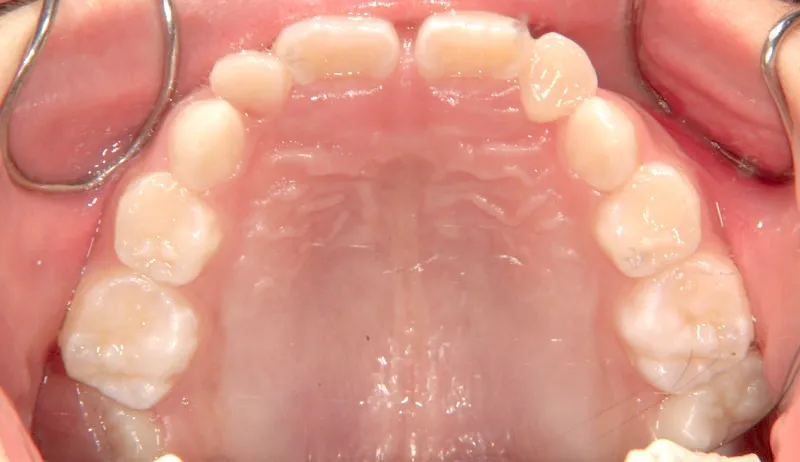

【子供の矯正(一期)】叢生・開咬・前歯で噛めない・舌癖・7歳女児【M.O様】

治療終了後

治療回数31回、4年11ヶ月の治療期間で矯正治療を終了しました。

主訴が改善され、ご満足頂きました。